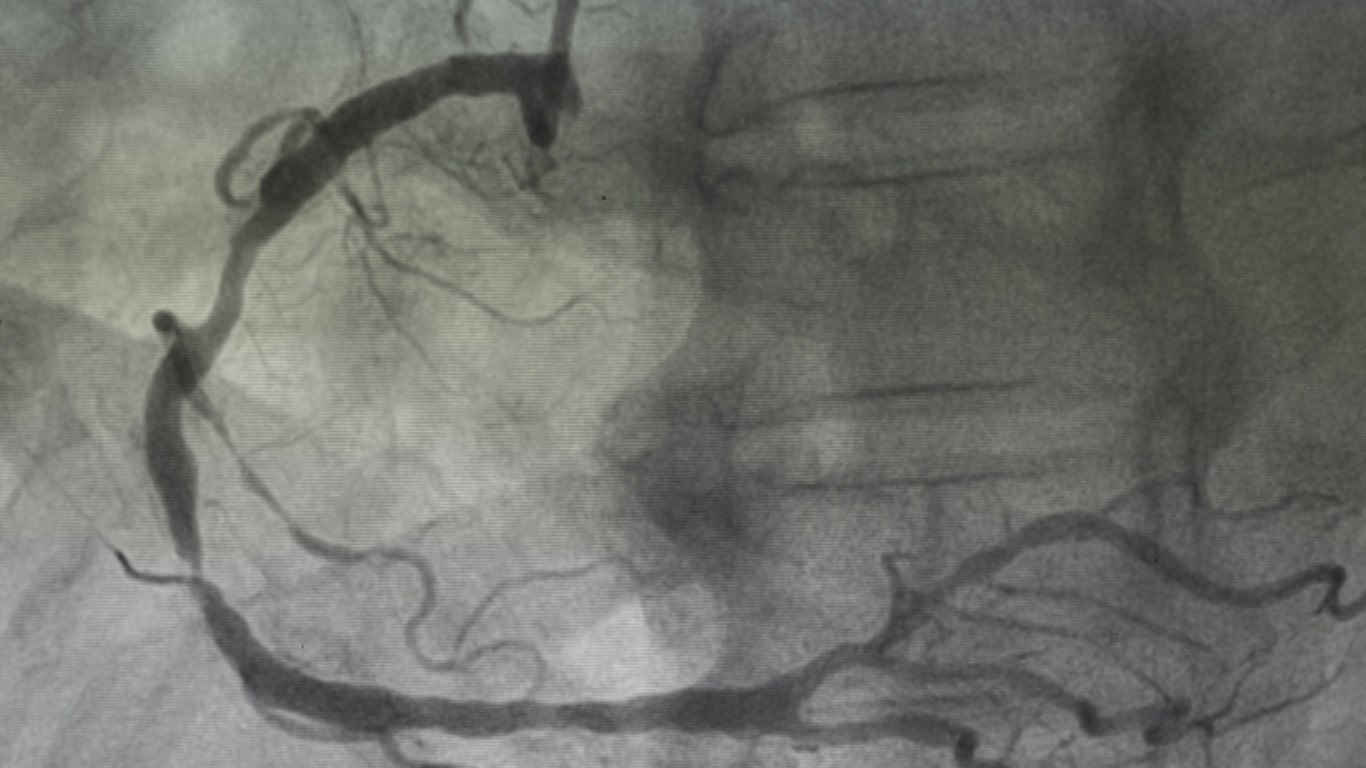

6.3. Chụp mạch máu số hóa xóa nền (DSA)

-

Là tiêu chuẩn vàng để đánh giá chính xác mức độ hẹp.

Tuy nhiên, đây là thủ thuật xâm lấn nên chỉ dùng khi có chỉ định điều trị can thiệp.